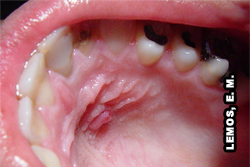

Edema localizado. Dente responsável 16 - abscesso apical agudo |

Edema localizado. Dente responsável 12 (raiz com curvatura apical distopalatina) - abscesso apical agudo |

Fístula palatina anterior esquerda. Dente responsável 22 (raiz com curvatura apical distopalatina), abscesso apical crônico |